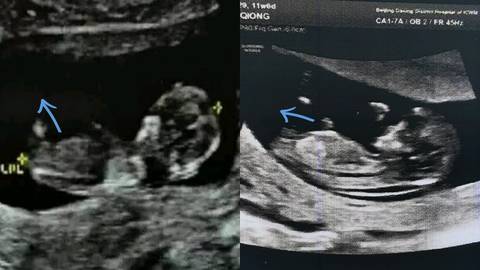

据说NT看男女很准呀,来凑热闹~左边图是儿子的(已证明准的),右边是二胎今天做的(好像是平行的唉🤔),希望凑成"好"❤,哈哈😄